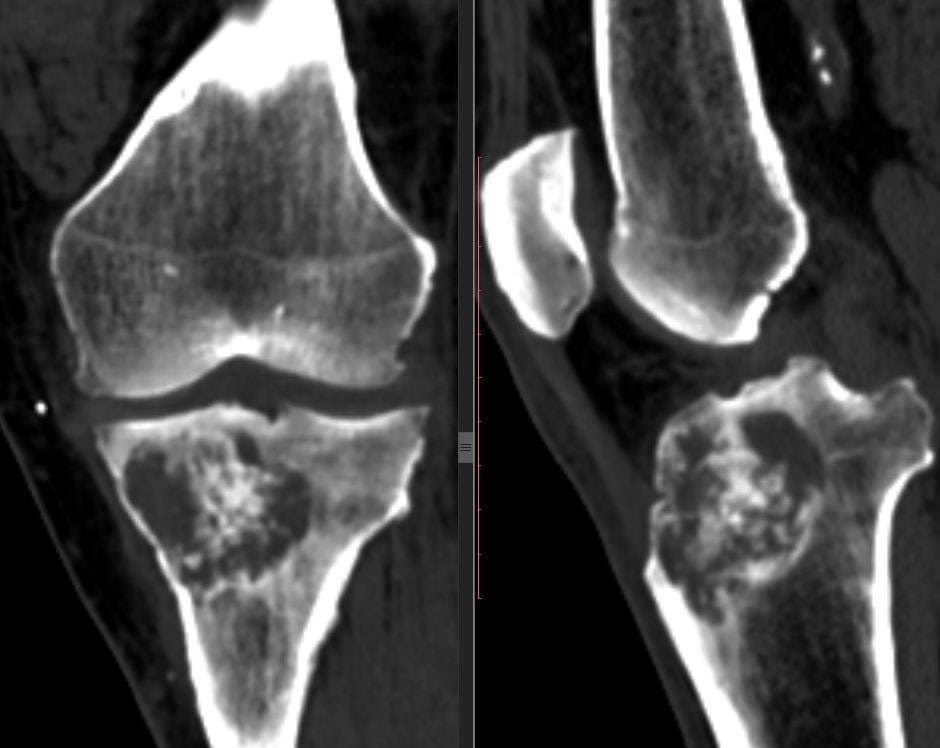

Симптомы туберкулеза коленного сустава

Первый признак патологии – это постоянные боли в колене, которые усиливаются при ходьбе, сгибании и разгибании ноги, ощупывании сустава. Периартикулярные ткани становятся отечными и уплотненными. Со временем симптомы становятся более выраженными.

По мере прогрессирования болезни у человека атрофируются мышцы и развивается сгибательная контрактура конечности. Из-за этого ему становится крайне трудно разогнуть ногу в колене. На поздних стадиях в околосуставных тканях могут формироваться свищи и абсцессы. При вторичном инфицировании сустава у больного могут развиваться острые артриты.

У лиц с легочным туберкулезом врачи выявляют заболевание легко. Для подтверждения диагноза они используют рентгенографию, КТ или МРТ. Немаловажное диагностическое значение также имеет обнаружение микобактерий в биоптате или гнойном отделяемом из свищей.

Костно-суставной туберкулез можно спутать с сифилисом, актиномикозом, остеомиелитом, хроническим артритом, злокачественным новообразованием или другими заболеваниями. Поставить правильный диагноз врачи могут лишь после обследования.